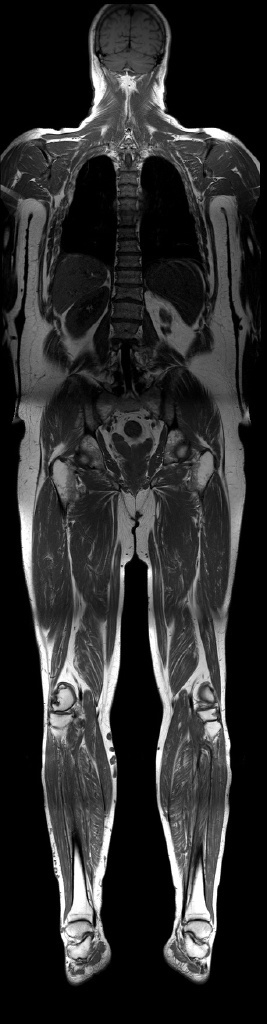

Ein Durchbruch ist jetzt mit der Entwicklung eines neuen Magnetresonanztomographen gelungen. Aufgrund eines neuen Hard- und Softwarekonzeptes kann der ganze Patient in deutlich kürzerer Zeit als bisher untersucht werden - sozusagen von der "Locke bis zur Socke". Es beruht auf der sogenannten "total imaging matrix", ein System aus bis zu 76 Empfangselementen, die das Signal aus dem Körper gleichzeitig empfangen und verarbeiten können. Damit wird die Messdauer auf einen Bruchteil der bisher erforderlichen Zeit reduziert.

Mit dem neuen Magnetresonanztomographen können in einem Untersuchungsgang Gehirn, Lunge, Bauch und Becken und das gesamte Skelettsystem dargestellt werden, so dass die Tumoren und deren Metastasen entdeckt werden (Abbildung 2). Eine spezielle Vorbereitung ist nur für die Untersuchung des Dickdarms erforderlich. Durch Medikamente und reichliche Flüssigkeitseinnahme muss der Dickdarm gereinigt werden. Bei der Untersuchung wird er dann über eine Sonde mit Flüssigkeit gefüllt. Die MRT-Daten können dann zu einer virtuellen Koloskopie "rekonstruiert werden", so dass man auf elektronischem Wege durch den Dickdarm "fliegen" kann, um dabei möglicherweise vorhandene Polypen oder Karzinome zu erkennen.